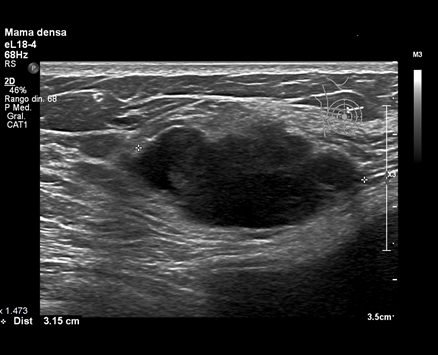

La ecografía mamaria es el método de imagen más utilizado en el estudio de la patología mamaria como complemento de la mamografía. Su utilización de forma conjunta ha demostrado una mejora en la precisión diagnóstica. Entre sus ventajas se encuentra el bajo coste, la accesibilidad y la ausencia de radiaciones ionizantes. Indicaciones: caracterización de masas palpables y no palpables, valoración de hallazgos clínicos y mamográficos, guía de procedimientos intervencionistas y estudio de mujeres con implantes mamarios. También ha demostrado su capacidad de caracterizar nódulos mamarios, ayudando a diferenciar lesiones benignas de lesiones malignas. Es la prueba de elección en el estudio axilar.